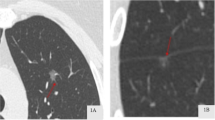

All chest CT examinations included the complete thorax and were performed in the supine position. Scans were obtained during deep inspiration and the patients holding their breath. The CT images were examined and interpreted by two radiologists with more than 5 years of experience in thoracic radiology. The two radiologists independently determined the characteristics of each image, while a third radiologist, with over 20 years of experience in thoracic radiology reassessed the measurements to check for discrepancies. Any discrepancies noted were resolved through discussion among the three radiologists. Central nodules were defined as those located in the bronchi, lobular bronchi, or segmental bronchi of the lungs, while peripheral nodules were defined as those located below the tertiary bronchi. Spiculation was defined as diffusion from the nodule edge into the lungs without contact with the pleural surface. Further, cavitation was defined as the presence of spaces filled with gas and considered regions of transparency or low attenuation. Pleural adhesion was defined as the linear attenuation of pleura or fissures from the nodule. Patterns in CT images, including delamination, central nodule, diffusion, or a popcorn pattern, were considered signs of calcification. A pulmonary artery passing through the nodule, as observed in the CT images was indicative of vascular penetration. Further, bronchial signs on the CT image showed direct bronchial engagement of the nodule. Lobulation was defined as a wavy or scalloped portion on the surface of a lesion, with strands stretching from the nodal edge to the lung parenchyma. Pleural effusion was defined based on a blunted angle of the rib diaphragm in the CT image. Lymph node enlargement was defined as a > 1-cm long lymph node axis in the CT image.

Previous studies have also demonstrated that the CT features of pulmonary nodules can be used to assess their aggressiveness. These imaging features included lobulation, spiculation, bronchus signs, cavitation signs, pleural adhesion signs, and nodule shape [24, 25, 27, 40,41,42,43,44,45,46,47,48,49,50,51,52]. Furuya et al. reported that 82% of lobulated nodules and 97% of acinar nodules are malignant [53]. Lobulation and spiculation of pGGN are also more common in invasive lesions than in pre-infiltrative lesions [18]. Further, Lee et al. found that lobulation is more common in IAC than in pre-infiltrative lesions [42]. However, lobulation was not included as a risk factor for malignant lung nodules in the Herder model [51]. In this study, we identified lobulation as a risk factor for the occurrence of IAC in pGGN; however, no significant differences were observed in this regard with respect to spiculation. A possible reason for this observation is the limited number of nodules with spiculations included in the study. The bronchus signs observed in this study constituted another CT feature that showed association with malignancy. Bronchial signs were more frequently observed in patients with malignant GGN than in those with benign GGN. Reportedly, patients with IAC present with bronchial signs more frequently than those with AIS [45, 54]. Thus, based on our results, bronchial signs were identified as significant predictors of IAC (P = 0.009).